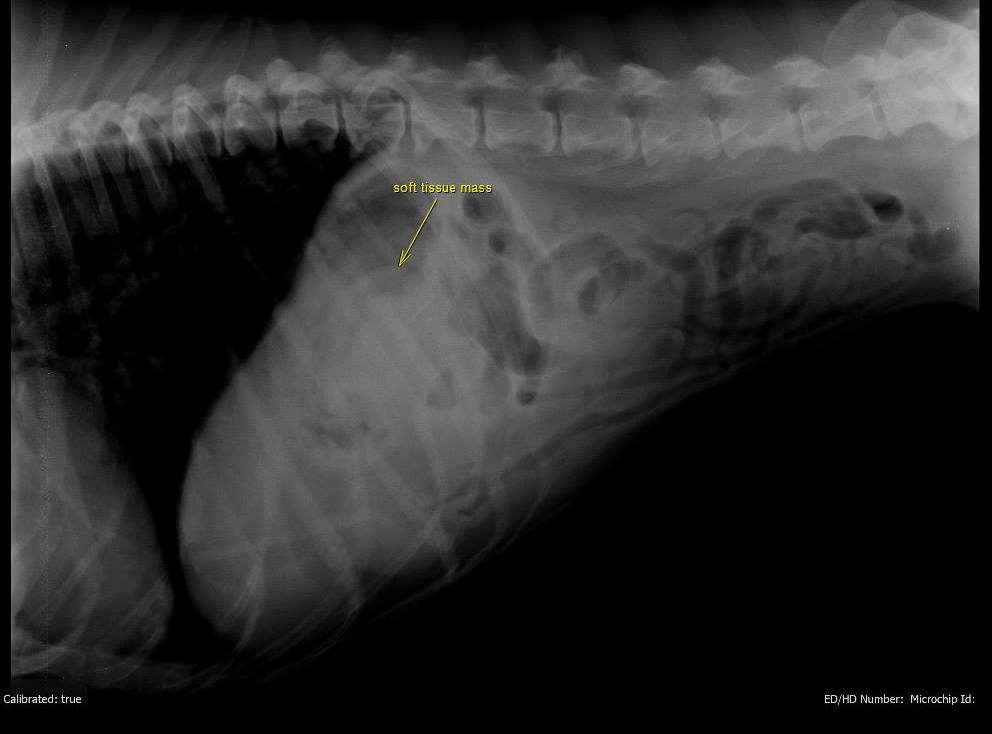

This is a case of a 10-year-old female spayed Boxer who has been anorexic intermittently for several weeks. Over the last week, the owner has had to syringe feed. Prior to onset, P was treated for cystitis, which resolved. Treatment for gastritis, including sucralfate, famotidine, and triamcinolone was only effective for a few days at a time. Chemistries on April 25 showed a slight elevation of lipase. CBC had very mild lymphopenia. Previous surveys' results were unremarkable for GI. Only 2 instances of vomiting have occurred during this time.

On the survey study you can see a soft tissue opacity in the stomach. However, be careful not to overinterpret this on a non-contrast image. Fluid in the stomach can often have this appearance and you can get a false impression of gastric wall thickening due to the air/fluid interface. However post adminstration of barium, we can now see a gastric mass causing a filling defect in the gastric wall on numerous images, and this confirms that what we saw on the survey images was a real finding. The contrast will surround the mass causing it to appear radiolucent and allowing us to define the margins. Primary differentials, particularly in this age and breed, would be neoplasia (lymphoma, adenocarcinomva).

Would you see this on ultrasound? Potentially, but it depends on your skill level in sonography, how much air is in the stomach, where in the stomach it is located, etc. So if you do not have access to ultrasound (or even if you do) or if you were unable to get a good view of the gastric wall this is a great study to do! Thank you to Dr. Greg Emmert (one of my vet school classmates!) and McGee Street Animal Hospital for this fascinating case!